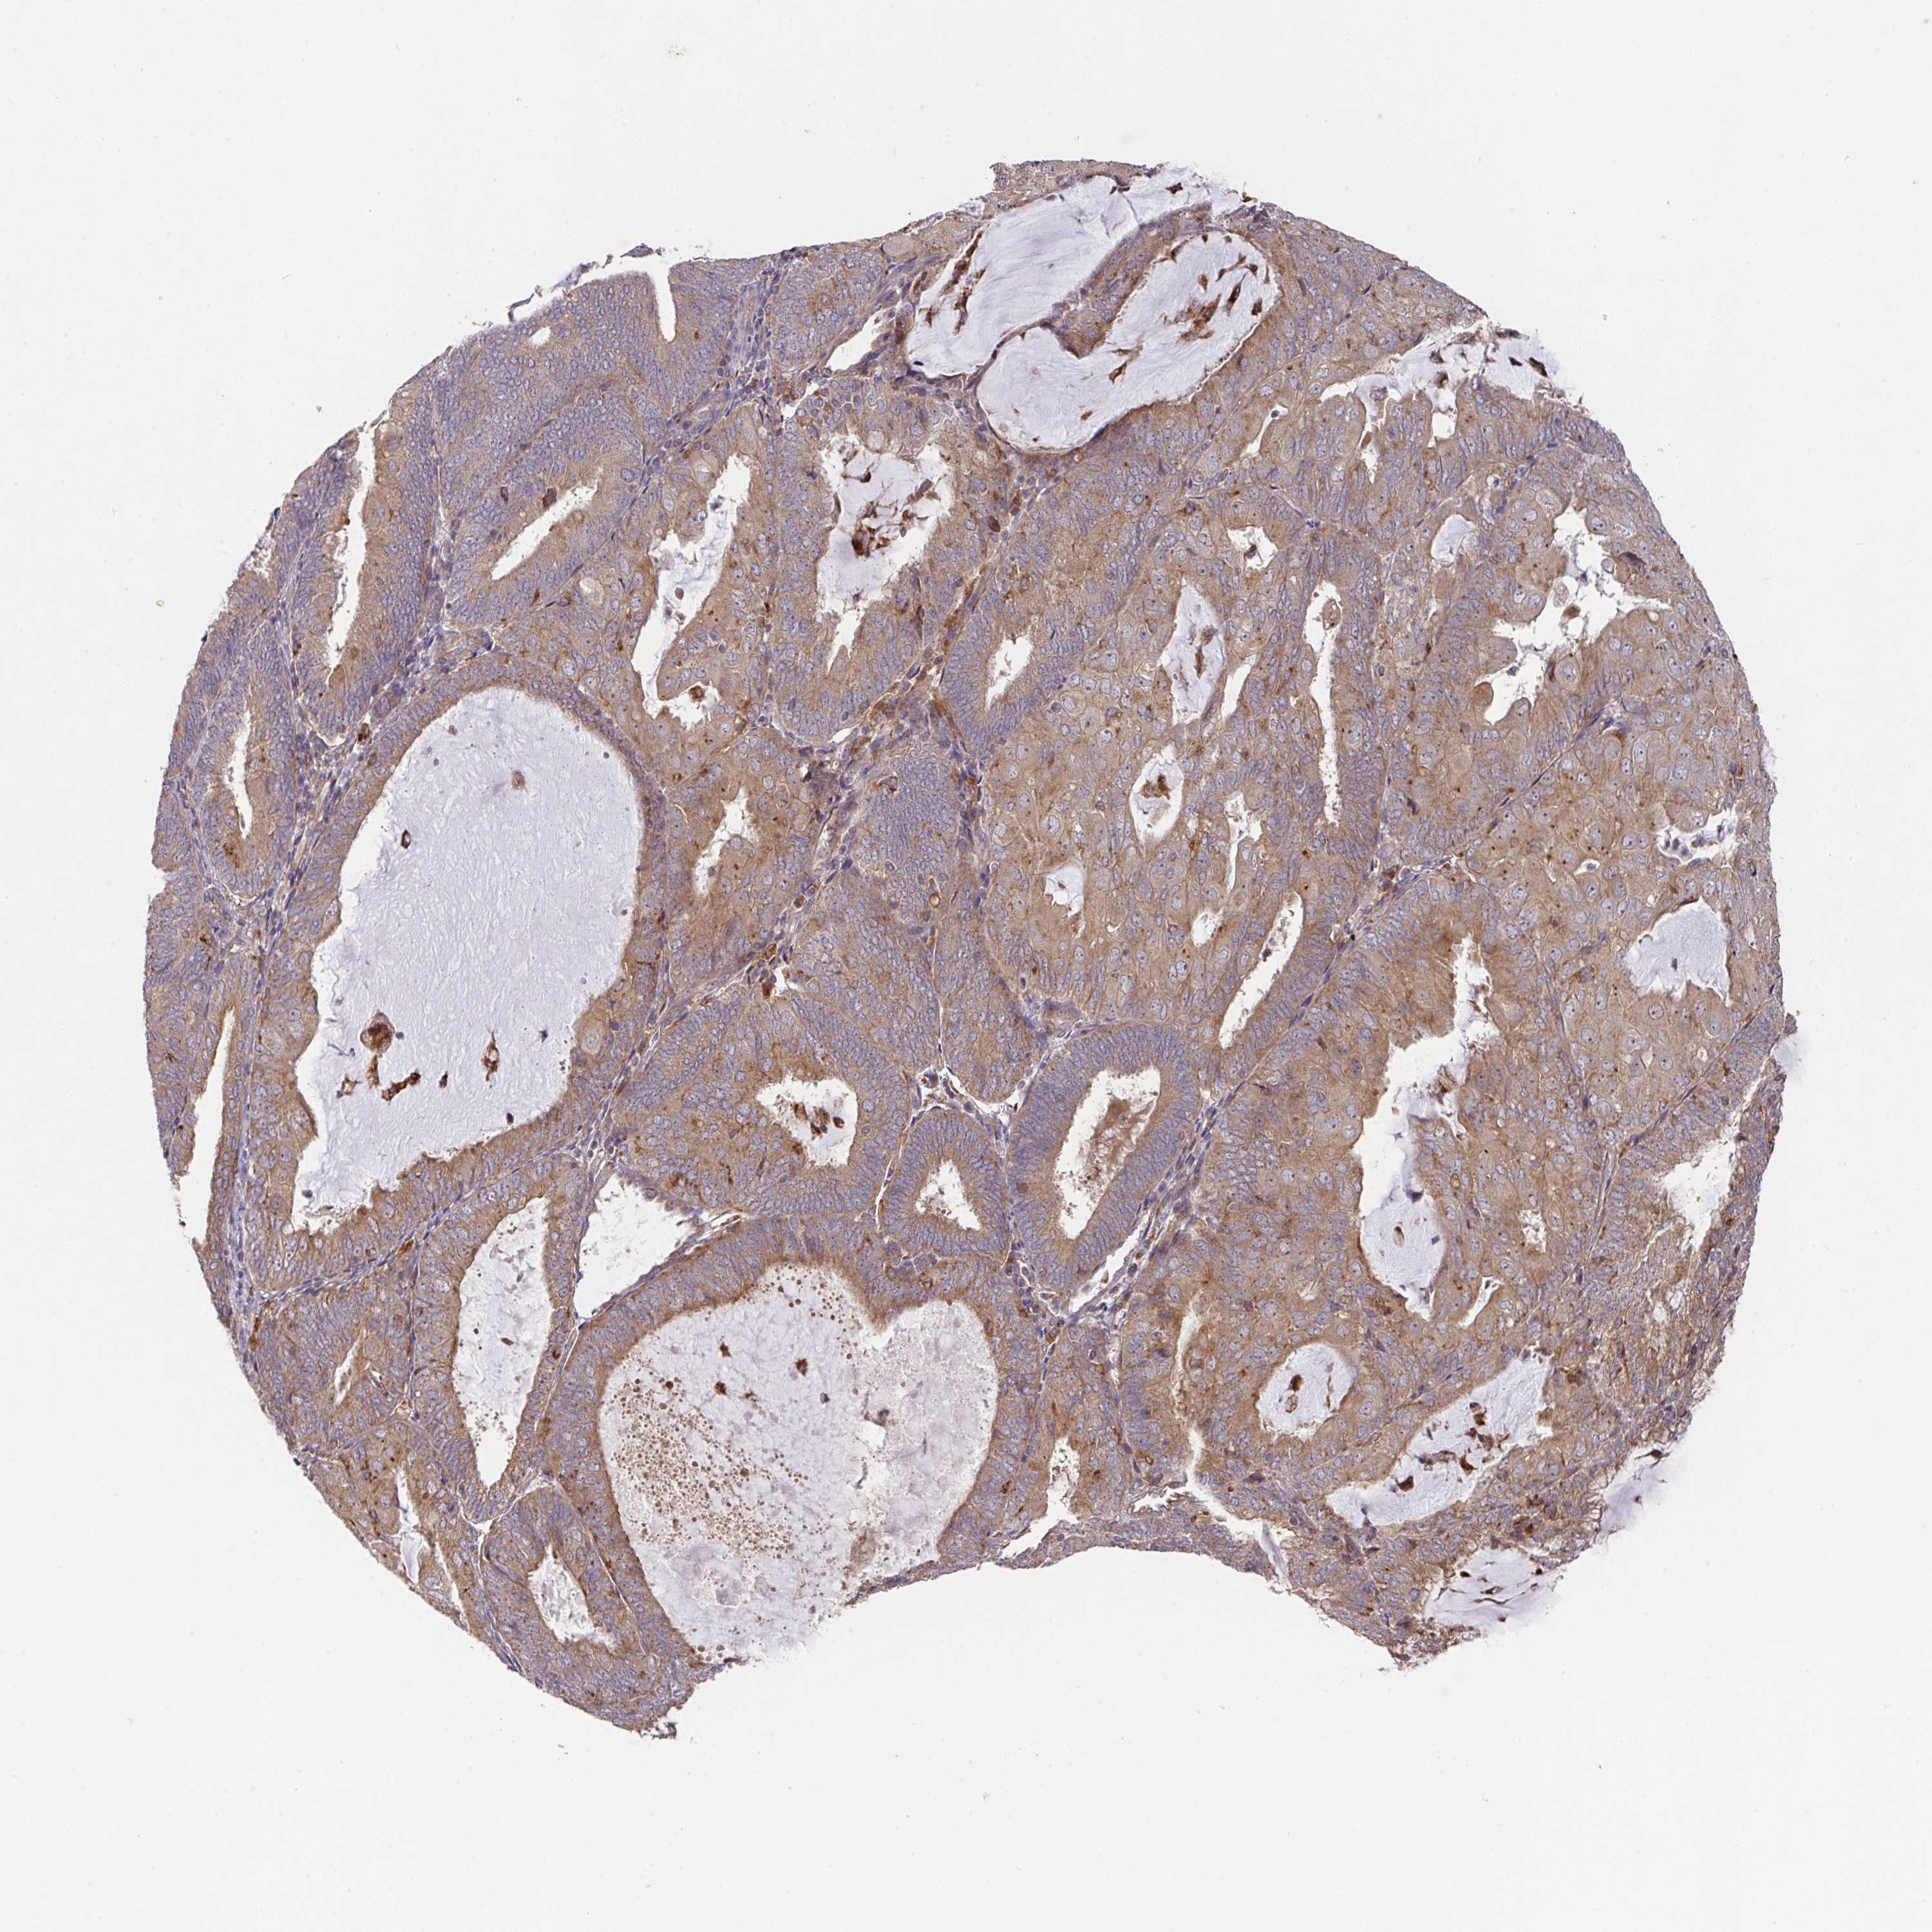

ENDOMETRIAL CANCER - Protein expressioni

A mouse-over function shows sample information and annotation data. Click on an image to view it in a full screen mode. Samples can be filtered based on level of antibody staining by selecting one or several of the following categories: high, medium, low and not detected. The assay and annotation is described here.

Note that samples used for immunohistochemistry by the Human Protein Atlas do not correspond to samples in the TCGA dataset.

Antibody stainingi

Antibody staining in the annotated cell types in the current human tissue is reported as not detected, low, medium, or high, based on conventional immunohistochemistry profiling in selected tissues. This score is based on the combination of the staining intensity and fraction of stained cells.

Each image is clickable and will lead to virtual microscopy that enables deeper exploration of all samples and also displays staining intensity scores, fraction scores and subcellular localization as well as patient and tissue information for each sample.

Antibody HPA053217

Staining

High

Medium

Low

Not detected

Intensity

Strong

Moderate

Weak

Negative

Quantity

>75%

75%-25%

<25%

None

Location

Nuclear

Cytoplasmic/membranous

Cytoplasmic/membranous,nuclear

Adenocarcinoma, NOS